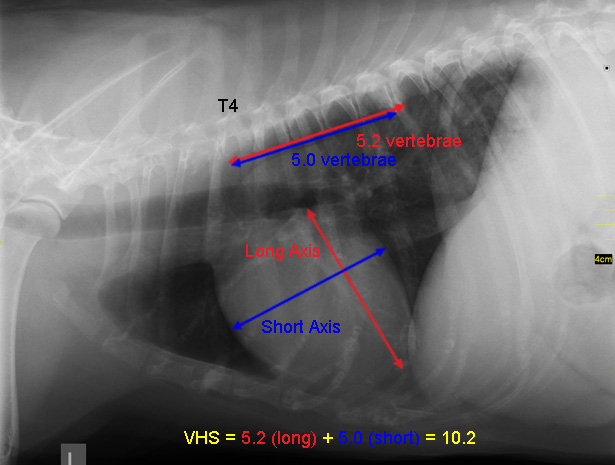

如上图,VHS=5.2v+5.0v=10.2v